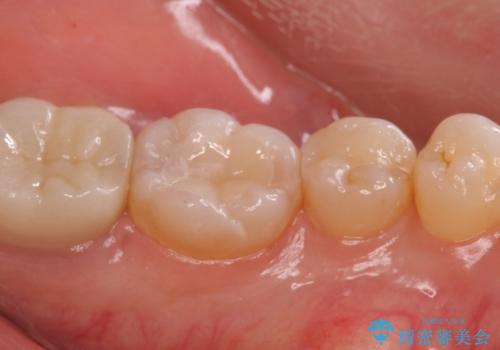

歯の噛む面が黒い。

- 歯の噛む面が黒いとのことで来院。

過去にプラスチック樹脂の治療がされており、プラスチックと歯質の隙間に汚れがたまり黒くなっていました。

劣化して黒くなりたくない、虫歯の予防がしたいとのご希望だったのでセラミックインレー(e-maxインレー)による治療を行いました。